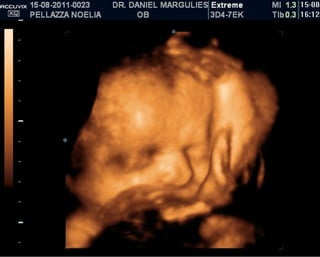

ISABELLA!

ISABELLA! Está viniendo!